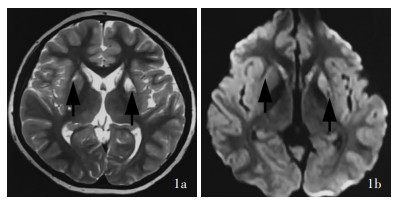

Ji K , Wang W , Lin Y , Xu X , Liu F , Wang D , Zhao Y , Yan C . Mitochondrial encephalopathy due to a novel pathogenic mitochondrial tRNA Gln m. 4349C > T variant. Ann Clin Transl Neurol, 2020, 7: 980- 991.